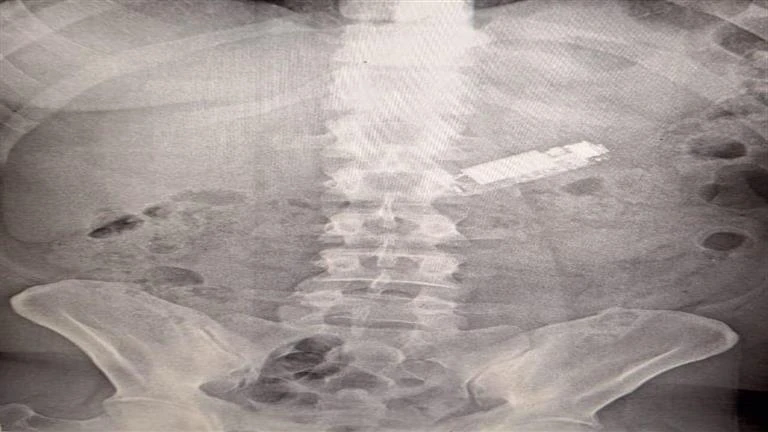

في واقعة غير عادية تثير الدهشة، نجح فريق طبي بمستشفيات جامعة طنطا في استخراج هاتف محمول من معدة مريض، بعد أن ظل داخلها لمدة 5 أشهر كاملة.

بدأت القصة عندما استقبلت وحدة الطوارئ بمستشفيات جامعة طنطا مريضًا في الأربعينيات من عمره، كان يعاني من ألم غير مفسر في معدته، وبعد إجراء الفحوصات الطبية اللازمة، تبين أن المريض قد ابتلع هاتفًا محمولًا عن طريق الخطأ، وكان الهاتف عالقًا في معدته طوال هذه الفترة.

استدعت الحالة إجراء أشعة عادية على البطن لتحديد مكان الهاتف، وأكدت الأشعة وجوده في المعدة، وبعدما أجرى الفريق الطبي المتخصص عملية منظار على البطن استمرت لمدة ساعة، تمكنوا من استخراج الهاتف بنجاح، وخرج المريض من المستشفى في حالة صحية مستقرة.